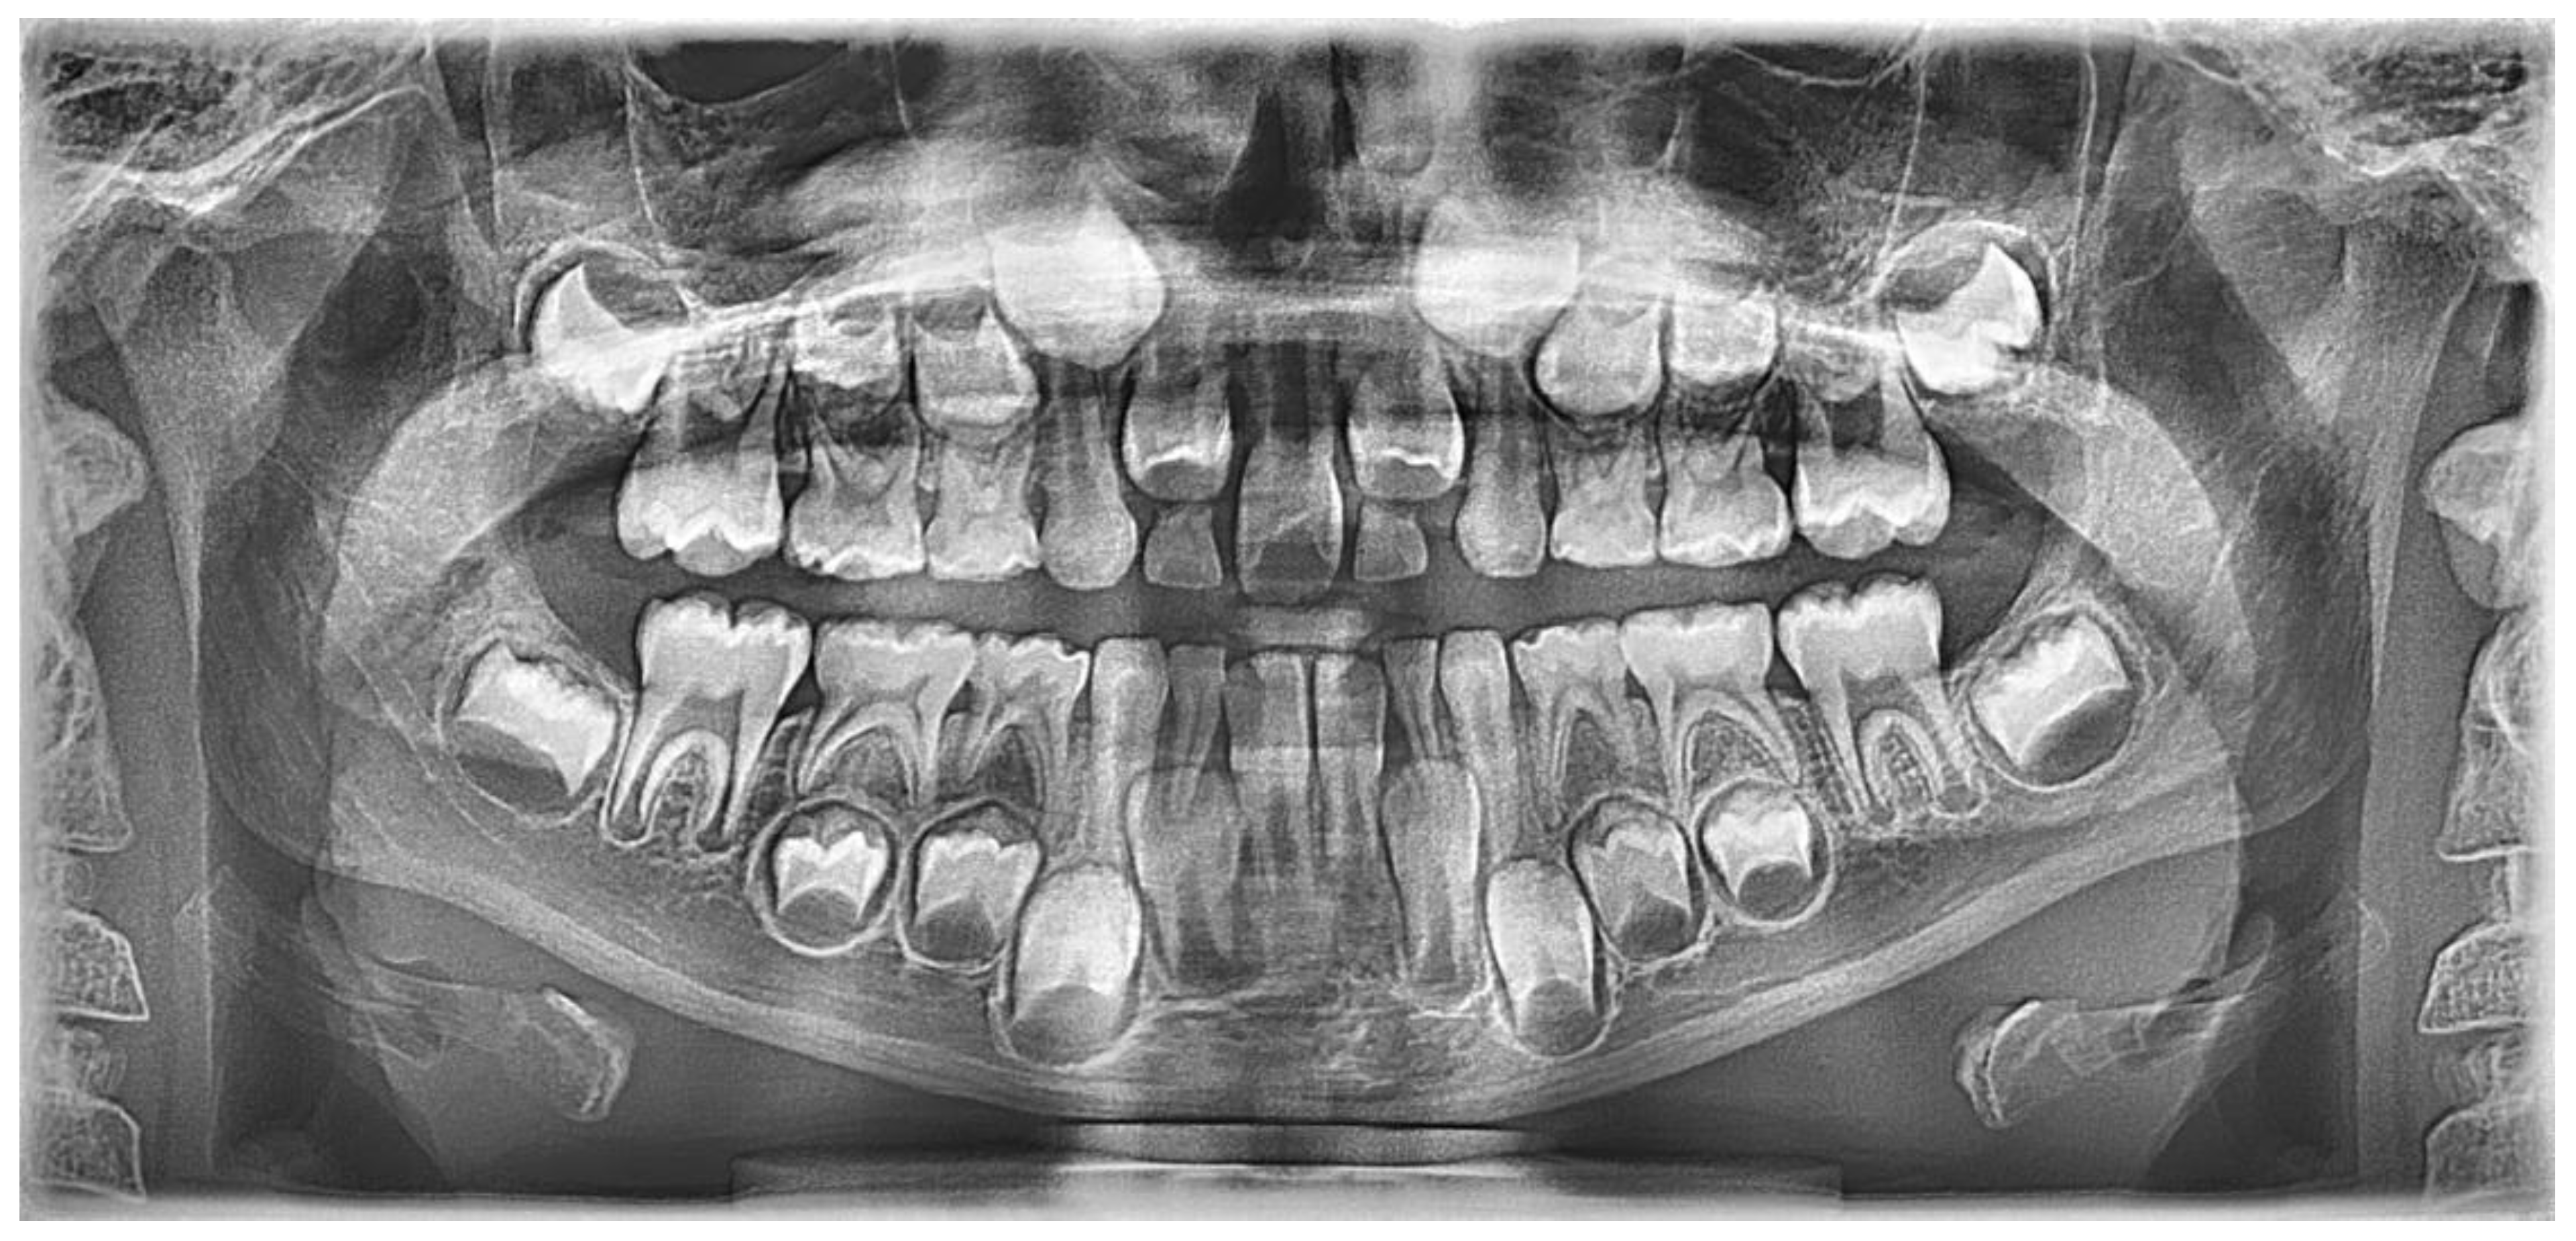

Case Description